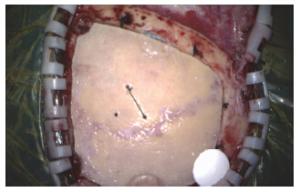

摘要 Objectives: In this case report, we describe the design, fabrication and clinical outcomes of a novel bioresorbable, mineralized collagen burr-hole plug for the reconstruction of craniotomy burr-holes.

Methods: Mineralized collagen burr-hole plugs were fabricated via a biomimetic mineralization process. The biomimetic mineralized collagen has a similar chemical composition and microstructure to natural bone tissue, thereby possessing good biocompatibility and osteoconductivity. The mineralized collagen burr-hole plugs were implanted into three patients, and clinical outcomes were evaluated at one-year follow-ups.

Results: All bone defects healed very well using the mineralized collagen burr-hole plugs, and there were no adverse reactions at the surgical sites.

Conclusions: The clinical outcomes indicated that the mineralized collagen was effective for reconstructing burr-holes in the skull after craniotomy.

Abstract: Objectives: In this case report, we describe the design, fabrication and clinical outcomes of a novel bioresorbable, mineralized collagen burr-hole plug for the reconstruction of craniotomy burr-holes.